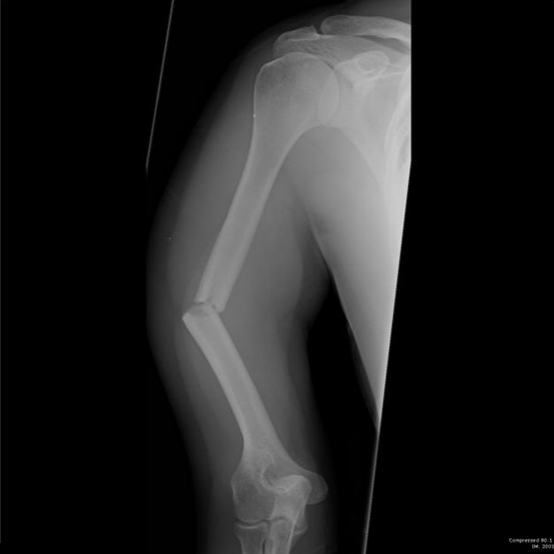

2

Q

What is the orientation of the fracture and the causative mechanism?

A

Spiral fracture due to rotation with axial compression